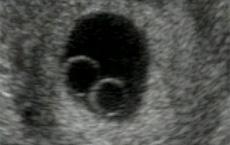

Dobrý den, otěhotněla jsem díky IVF cyklu, transferována byla dvě embrya kvality BC (punkce 12.7., transfer 17.7.). Měla bych být tedy v osmém týdnu a včera (lékař to spočítal jako 7+3) jsem byla na ultrazvuku, který u mne objevil jednu gestační dutinu a v ní dva vaječné váčky (viz přiložená ilustrační fotografie; nejedná se ale o snímek mého ultrazvuku, ale z netu staženou fotografii ultrazvuku jednovaječných dvojčat v jednom gestačním váčku v 7. týdnu těhotenství; já jsem v osmém týdnu, ale stav v mé děloze byl více méně přesně tento). Lékař také nezachytil srdeční ozvy a ty by se snad měly objevovat už od šestého či sedmého týdne. Lékař se vyjádřil v tom smyslu, že to nevypadá úplně normálně, že buď budu mít jednovaječná dvojčata anebo bude nutná evakuace plodu. Chci se zeptat: je skutečnost, že se na ultrazvuku dosud neobjevila srdeční činnost, znamení tak špatného vývoje, že bude třeba mé vytoužené těhotenství přerušit nebo mám ještě naději, že se vše začne vyvíjet správně? Stejně tak: je fakt, že u mne v osmém týdnu vypadá gestační váček s vaječnými váčky jako by byl teprve na úrovni sedmého týdne, znamení špatného vývoje plodu?) Na další ultrazvuk mám jít až 30.8. Denně užívám 3x Estrofem, 1x Crinone 8%, 1x acidum folicum, 1x Fragmin 2500 j. Budu Vám velmi vděčná za odpověď. Potřebuji vědět víc, abych se se vším dokázala vyrovnat anebo naopak nepropadala zbytečné skepsi, která by plodu nijak nepomohla. Marie W.